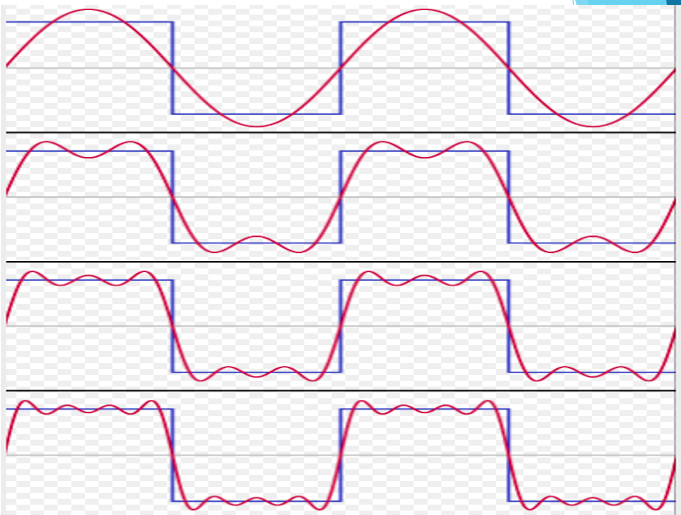

Il limite di questo tipo di stimolo è dato dal Fenomeno dell’Assuefazione. Avendo, il segnale elettrico, sempre le stesse caratteristiche in ampiezza (intensità in mA), frequenza ( in Hz ) e larghezza dell’impulso ( in ms o us ), per tutto il tempo di trattamento, la cellula si abitua alla tipologia di stimolo finchè non reagisce più allo stesso, diluendo sempre di più gli effetti positivi del segnale.

I vari generatori di corrente terapeutica classiche ( Tens, Interferenziale, Diadinamica, etc.) hanno un’azione che risulta essere sempre costante nei valori delle variabili ( Intensità, Frequenza, Larghezza d’Impulso) e non tengono conto delle risposte bioelettriche del tessuto.

Con il sistema Elettro-Neuro Feedback ENF, i processi descritti sono ottimizzati perchè il sistema retroazionato registra la risposta del tessuto agli stimoli, attraverso la trasposizione in superficie di una variazione di impedenza dettato dallo stimolo elettrico alla cellula, facendo sì che il generatore elettrico adegui il segnale di stimolo istante per istante.